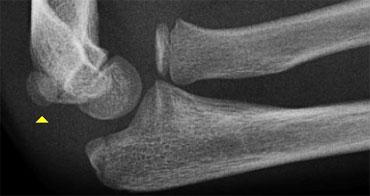

Normal medial epicondyle projecting posteriorly. Notice radial head dislocation and olecranon fracture

Medial Epicondyle avulsion

Mỏm trên lồi cầu trong là một mấu xương vì nó không đóng góp vào sự tăng trưởng theo chiều dọc của xương cánh tay.

Nó nằm ở phía sau của khuỷu tay.

Trên hình chiếu thẳng bên, đặc biệt nếu cánh tay ở tư thế xoay trong, nó có thể chiếu ra phía sau đến mức có thể gợi ý một tổn thương bong điểm bám (hình ảnh).

Tuy nhiên, các tổn thương bong điểm bám thường nằm ở vị trí xa hơn và phía trước hơn.